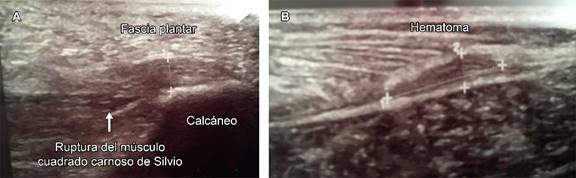

Figura 1: Imágenes de ecografía de zona plantar, se muestra afectación de la fascia plantar con una zona hipoecogénica que afecta al borde superficial, estructura fibrilar, borde profundo con presencia de hematoma compatible con ruptura. Al realizar movilización activa de la musculatura propia del pie, el músculo cuadrado de Silvio presenta retracción sin relación con la porción proximal de la fascia.